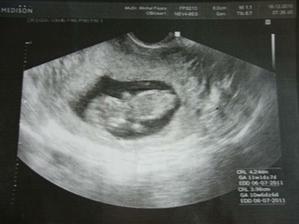

23.2. 2011 Byli jsme na velkém UTZ, ukázala se nám krásná zdravá holčička a pěkně čiperná 🙂